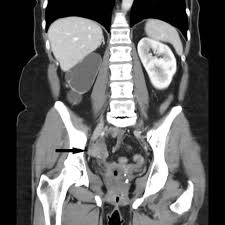

Cureus Appendicitis Caused By Endometriosis Within The Bowel Wall from assets.cureus.com Plain film radiography, computed tomography (ct) scanning, and barium studies are not sensitive for the diagnosis of endometriosis. Detection and localization of deep endometriosis by means of mri and correlation with the enzian score. The most common symptom is pelvic pain. Ct hrct is the modality of choice for thoracic endometriosis, which may demonstrate presence of pneumothorax, hemothorax or nodules which may change in nature cyclically. Tell the healthcare provider if you have ever had an allergic reaction to contrast liquid. A ct or mri may show the endometriosis. This type of endometriosis is called, deeply infiltrating or deeply infiltrative endometriosis die because it is found deep within the tissue or organ. Endometriosis is a condition in which the inner lining of the uterus (endometrium) grows outside the uterus in locations such as the fallopian tubes, ovaries, bladder, or other structures in the pelvis, causing pain, irregular bleeding, and possible infertility

Although the ovary is the most common site of involvement, endometriotic implants may occur in other locations outside the pelvis.

The most common symptom is pelvic pain. Plain film radiography, computed tomography (ct) scanning, and barium studies are not sensitive for the diagnosis of endometriosis. This type of endometriosis is called, deeply infiltrating or deeply infiltrative endometriosis die because it is found deep within the tissue or organ. Endometriosis is an important cause of chronic pelvic pain and infertility. The most common symptom of thoracic endometriosis is chest pain occurring right before or during menstruation. To diagnose endometriosis in the bowel, a physician conducts an examination that includes a vaginal examination, ultrasound, and a ct or mri scan. You may be given contrast liquid to help your abdomen show up better in the pictures. Tell the healthcare provider if you have ever had an allergic reaction to contrast liquid. Endometriosis is derived from the word endometrium, which is the tissue that lines the uterus. Endometriosis is defined as the presence of endometrial glandular and/or stromal cells outside of the uterine cavity. Learn about treatment, causes, stages, surgery, and diagnosis. The ct and mr characteristics of abdominal wall endometriosis are nonspecific, both showing a solid enhancing mass in the abdominal wall. The most common sign of endometriosis is pain in your lower belly that doesn't go away.